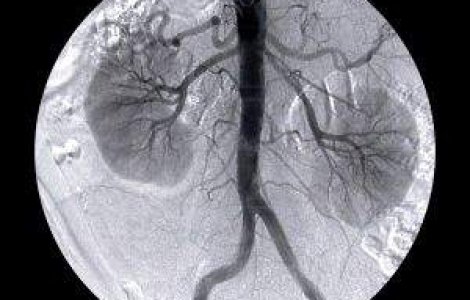

Tot mai multă lume încearcă să scape de medicamentele pe bază de chimie și să recurgă la metode tradiționale, naturale, care nu le vor afecta atât de mult organismul. Litiaza renală sau pietrele la rinichi este una dintre cel mai des întâlnite afecțiuni. Acestea se formează în interiorul rinichilor. Calculii cei mai întâlniți se formează din acid uric, oxalat și fosfat de calciu.